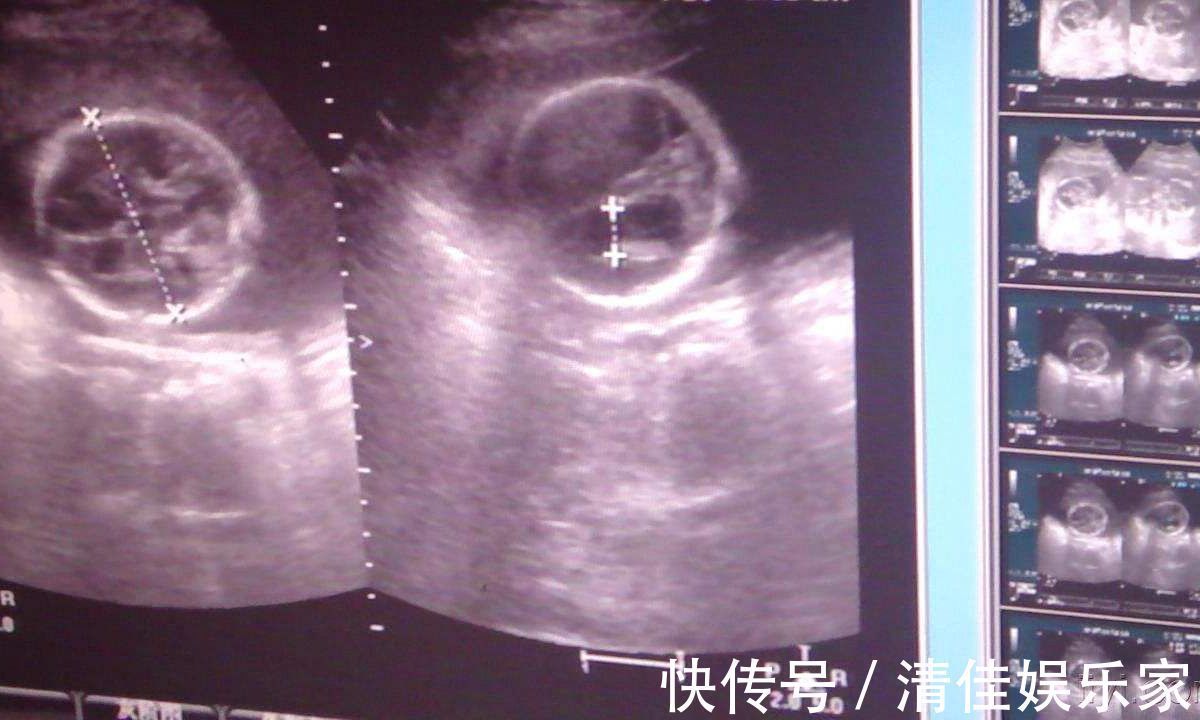

胎宝宝的生活的大人一样,同样离不开吃喝拉撒。“吃喝”是通过脐带传送满足对营养物质的需求,这一点无需强调。但是,除了丰富多彩的运动生活,妈妈们是不是也很好奇,胎儿会不会有大小便行为呢?如果有,那这些大小便跑到哪里去了呢?可以很确定的说,“小大人”也是有大小便的哦!但是,说到这些排泄物的去处,就有点大煞风景了。因为不断的吞吐羊水,所以胎宝宝也会有尿液产生,大概会在9周左右开始,胎儿会产生尿液,而这些尿液会被排放到羊水里面,最终再被自己“回收利用”哦!虽然这样的情况听起来有点小恶心,但其实胎儿生活在妈妈的肚子里面,他的尿液跟食用五谷杂粮的成人不同,是不会对身体产生危害的哦!

与尿液一样,胎宝宝既然在不停的吸收营养物质,那么也是会有排泄物产生的,虽然不是真正意义上的大便,但是那种深绿色的粘稠排泄物就是胎儿的粪便,也叫做胎便。正常的胎儿不会在妊娠期间排便,他们会将这种绿色粘稠物储存在肚子里,出生之后两三天左右就会排干净。胎儿的一切活动都是在羊水中进行,所以,与干净的尿液不同,一旦在孕期排出胎便,羊水就会被污染,会对胎宝宝的生命造成威胁。所以,孕期的宝妈们应该按时进行产检,以免胎儿在肚子里发生危险。